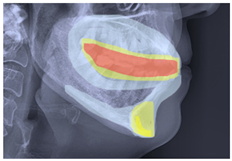

2.3. ROI Identification, YOLO-UNet-Based

4.4. CBCT Analysis Discussion